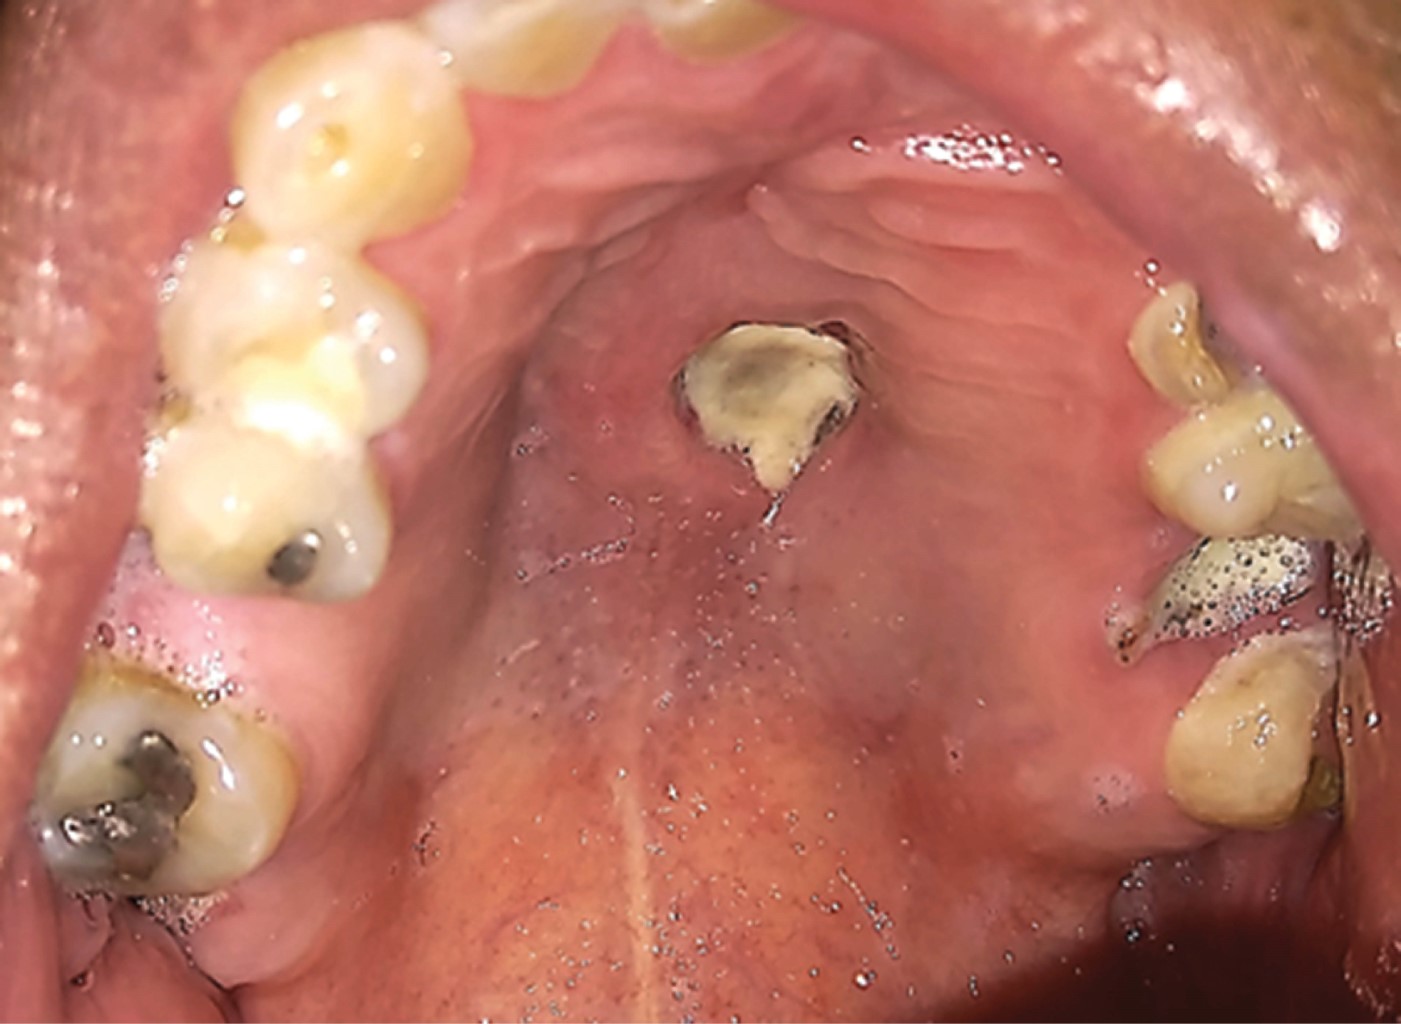

Rhino-orbit-cerebral mucormycosis with palatal manifestation, in a diabetic patient. Apropos of a clinical case and review of the literature

Mucormycosis is a rare, acute and frequently lethal disease caused by aerobic saprofit fungi and opportunists of the Mucoromycotina subdivision (before Zygomicota). Several clinical presentations have been described: rhino-orbital-cerebral, pulmonar, gastrointestinal, mucocutaneous and disseminate, rhino-orbital-cerebral mucormycosis (ROCM) is frequently associated To diabetic patients with inadequate control or hematological diseases. The rhino-orbital-cerebral presentation has a quick development with high morbidity and mortality in immunocompromised patients, with the need of a multidisciplinary medical and surgical approach. Case report of a patient with rhino-orbital-cerebral mucormycosis associated to uncontrolled diabetes mellitus DM2, palatine and cutaneous invasion, who was surgically treated with total bilateral maxillectomy, showed no evidence of recurrency in the next 16 months of follow up.

Figure 2